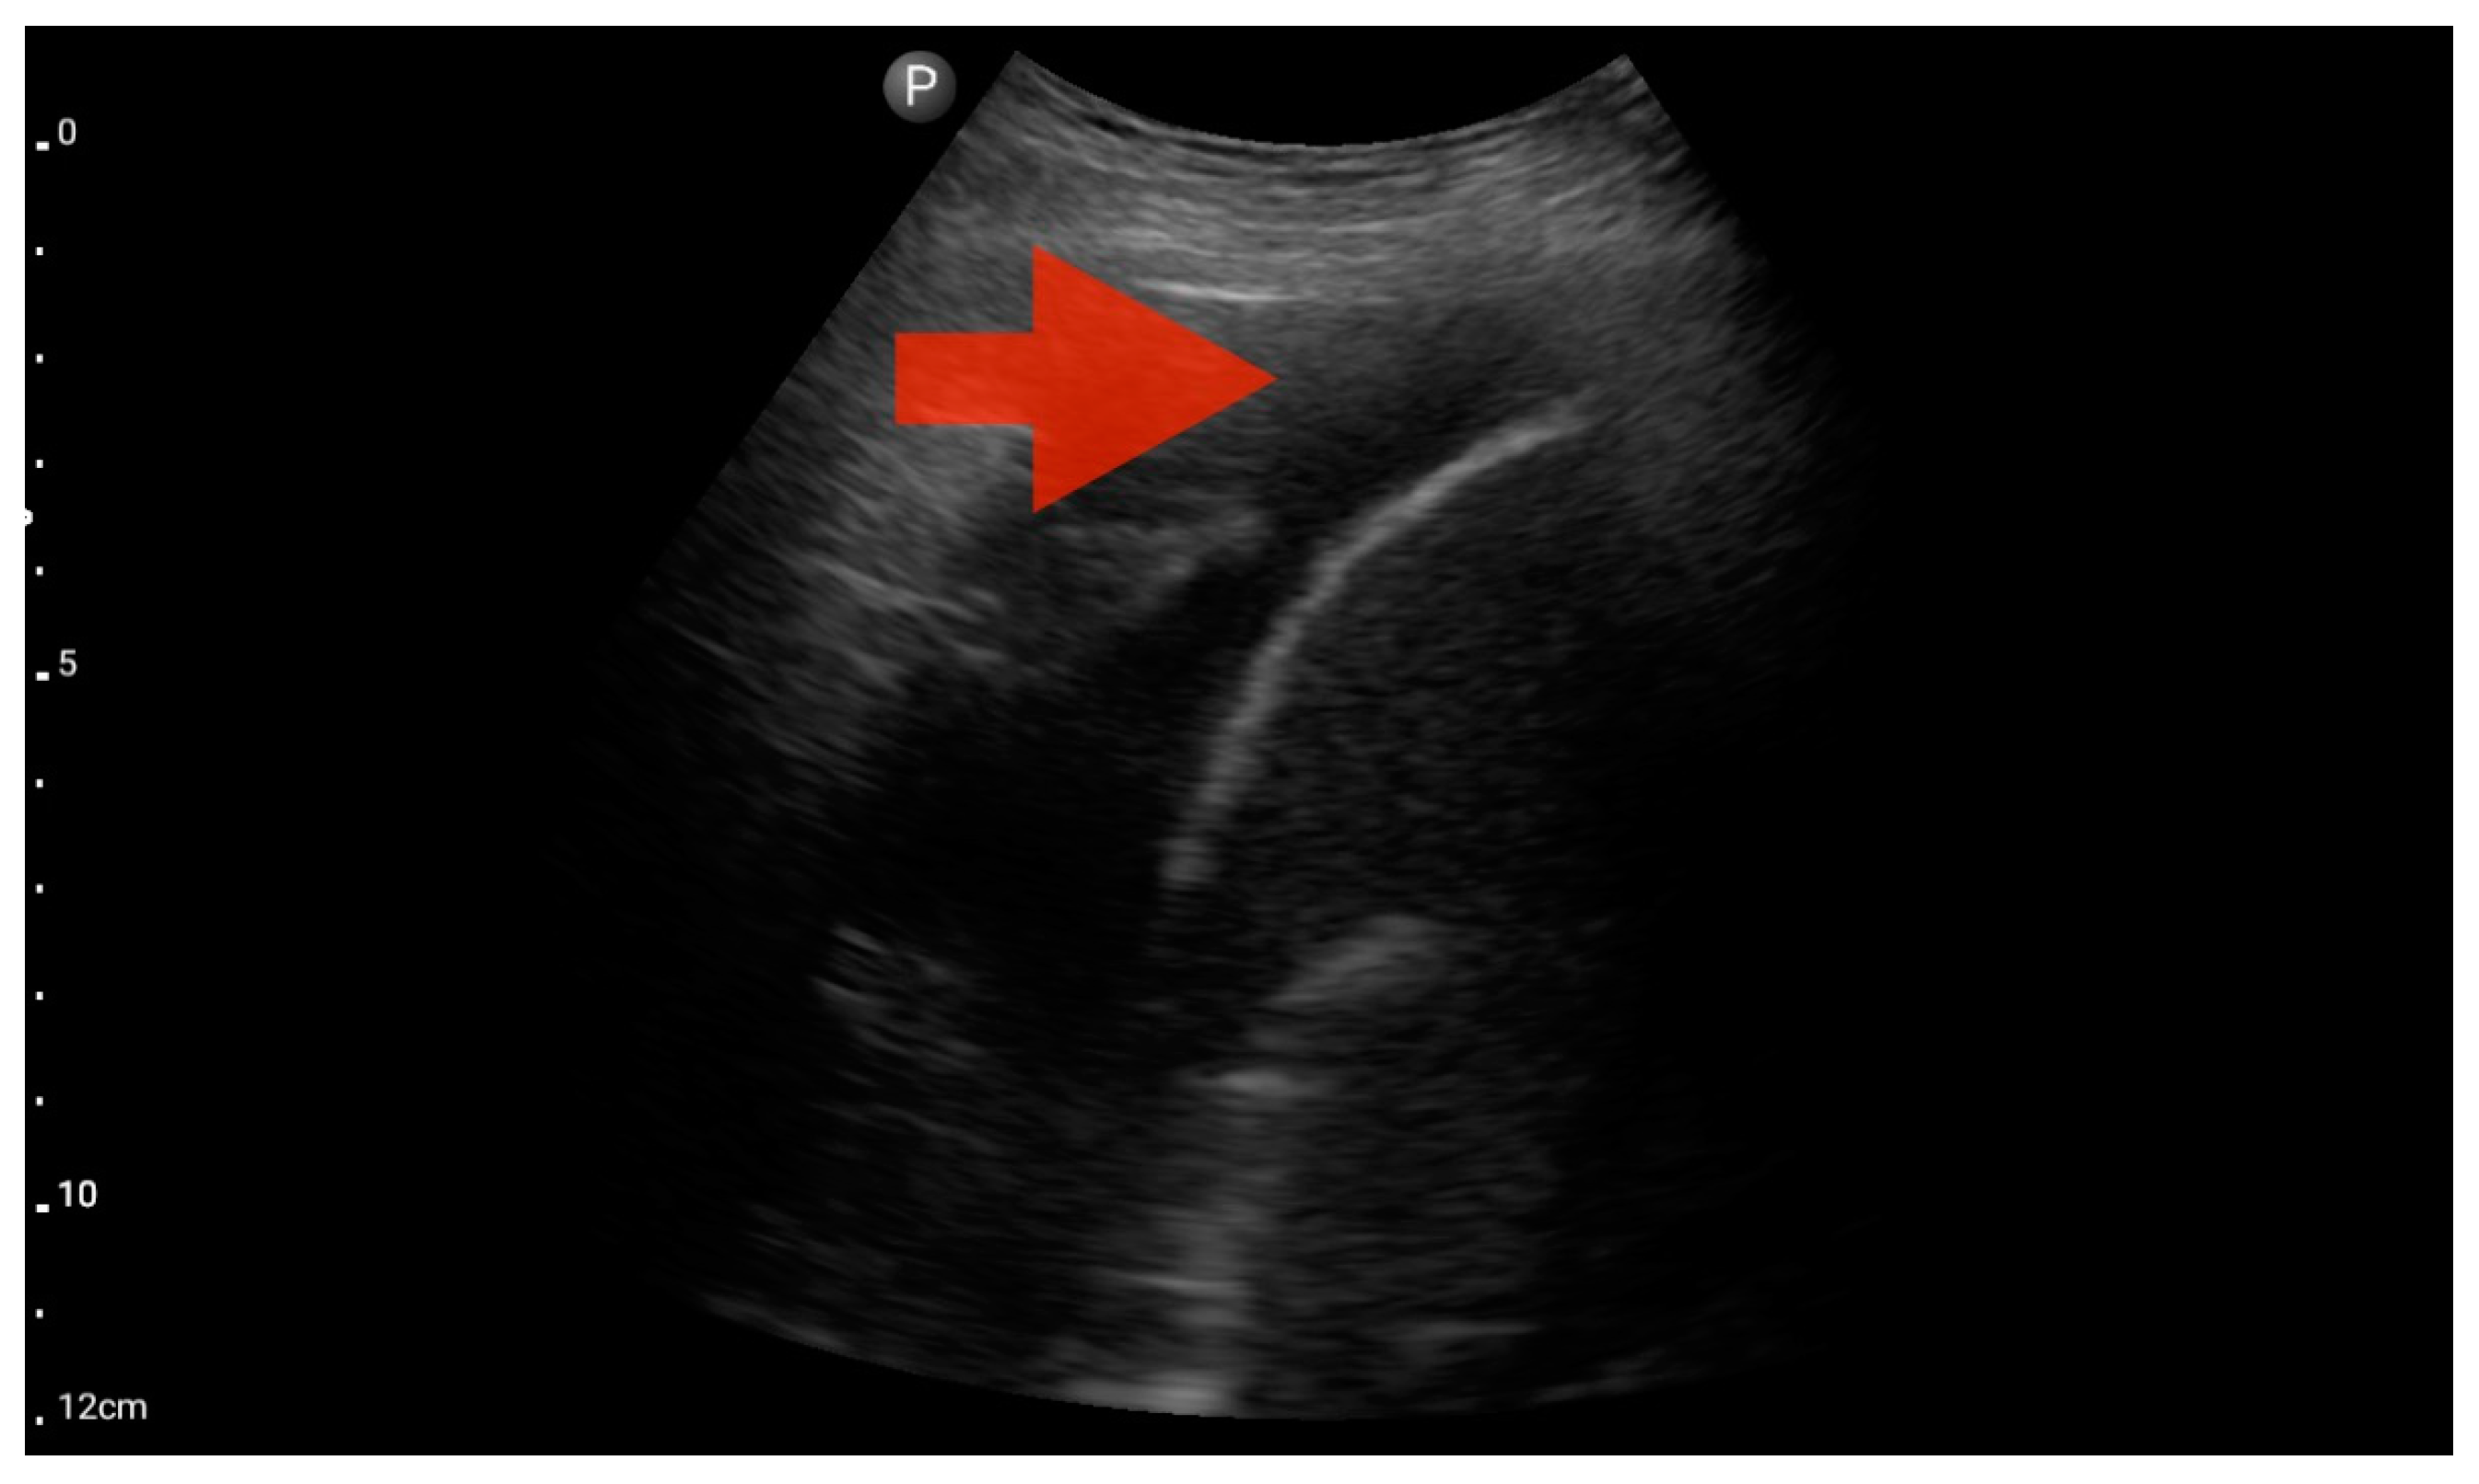

Figure 9.

Profile C (BLUE protocol). Convex probe examination, the middle part of the lung (5–7th intercostal); the red arrow indicates subpleural consolidation (source: author’s material—DK).